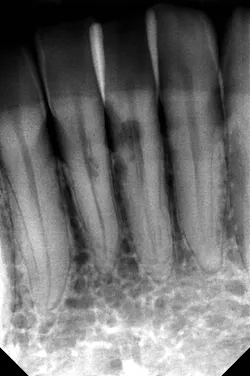

CBCT imaging or taking angled radiographs can help determine which type of resorptive process is being presented. Periapical radiographs are not great at giving you an accurate picture of the lesion’s size,4 but if you discover a possible resorption lesion upon clinical examination, you can use a periapical radiograph to determine if the lesion is indeed external or internal.

Start by taking a baseline radiograph of the lesion using a paralleling technique and a beam-aiming device, such as a Rinn instrument. With your second periapical radiograph, make a mesial horizontal shift with the tube head. If the process is on the tooth’s external surface, the resorptive lesion will move as the radiograph is shifted. Internal resorptive processes will always stay centered in the tooth when the angle is changed (figure 2). With external resorption, one canFinding a “pink spot” during an exam can be a little disheartening. Clinicians never like to deliver bad news or have to prepare a patient for a poor prognosis. Luckily, the incidence of both of these conditions is low; however, early diagnosis and treatment are always best to ensure your patients’ health and retention of their teeth. Cheers!